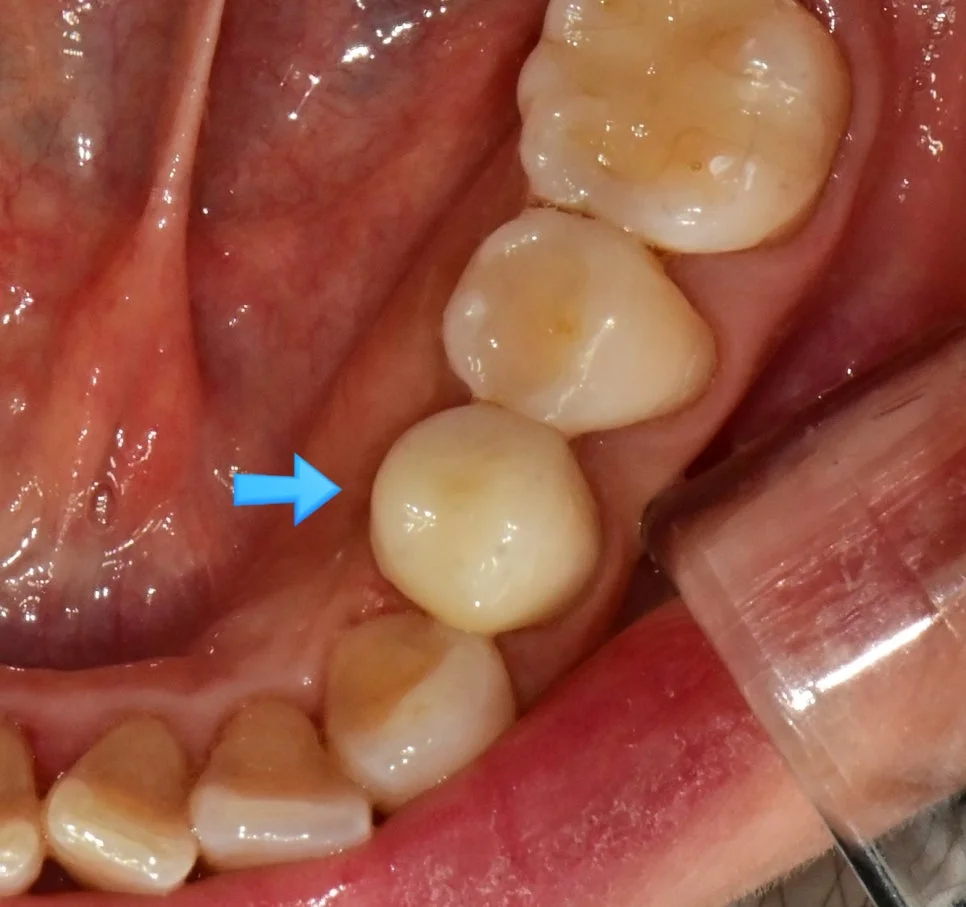

왼쪽 아래 잇몸의 통증을 호소하신 환자분입니다.

임플란트 음식물 끼임 잇몸 부음 사진

음식물이 고여 있고 주변 잇몸이 부어있는 상태

임플란트와 인접 치아 사이 틈새

임플란트와 바로 앞 치아 사이가 문제

사진을 보면 음식물이 고여 있고 주변 잇몸은 많이 부어있는 양상인데요. 임플란트와 그 바로 앞 치아 사이가 문제입니다.